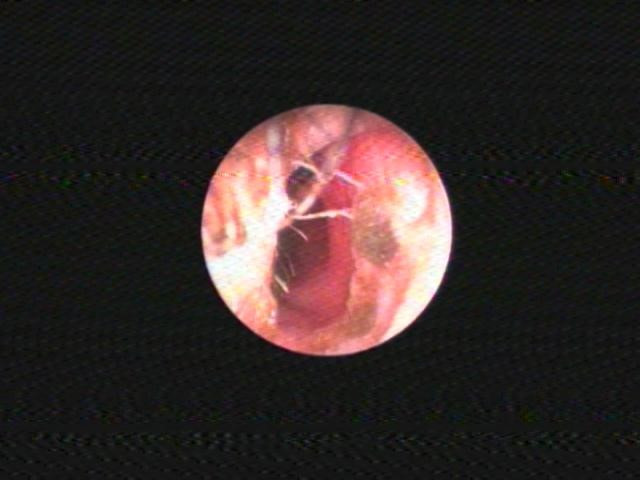

Các bác sĩ đã nội soi phát hiện mũi trái bé H. có một dị vật nằm bên trong đang trong quá trình gây viêm, tạo mủ. Ngay sau đó, các bác sĩ nhanh chóng gắp thành công 1 dây thun buộc tóc ra khỏi mũi trái cho bé H. Hiện tại, bệnh nhi đã ổn định và không chảy mũi.

![]() |

| Theo BS Lâm Lê Phương, Trưởng khoa Nhi - Bệnh viện Hoàn Mỹ Sài Gòn, dị vật mũi là bệnh thường gặp trong cấp cứu Tai Mũi Họng, đặc biệt hay gặp ở trẻ em. |